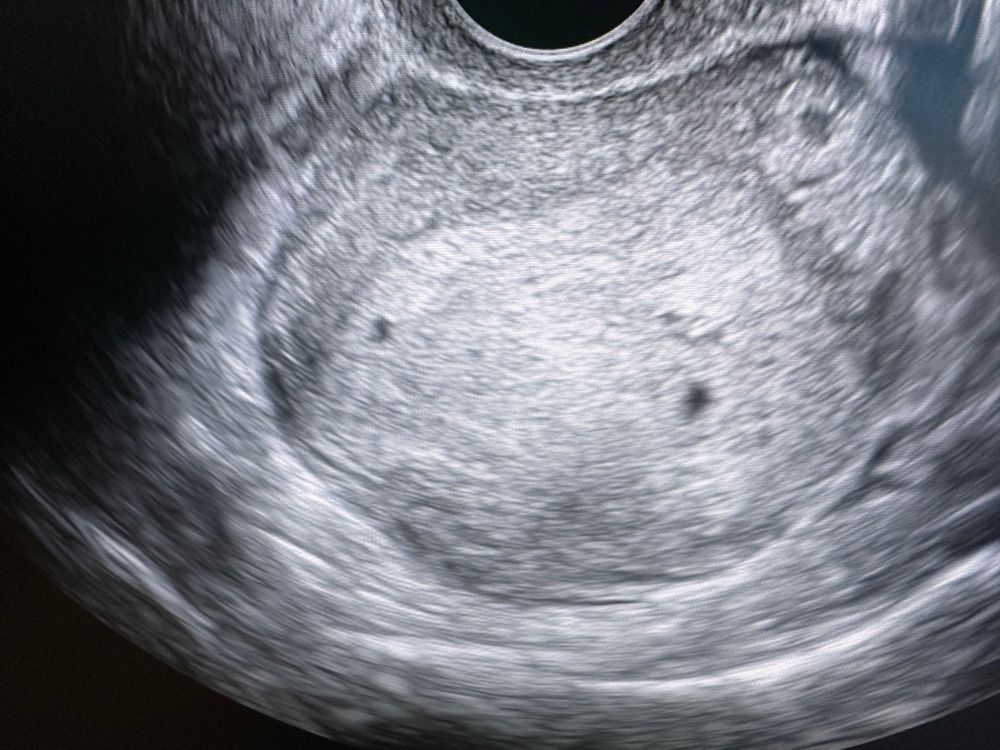

На узи была было 5 недель ровно, сегодня 5.4 Изображение

Виктория, мне кажется это два😅

Лита, мне показалось, что для одного много, я насчитала 8 тыс на сегодня) и на узи что-то непонятное

Наталья , во вторник на узи, так что обязательно тут выложу что в итоге, просто у меня подозрения не только из-за хгч, но и из-за узи, там четко два круголя, и матка узист сказал большая не на мой срок. Так что загадка и мистика)) самой интересно